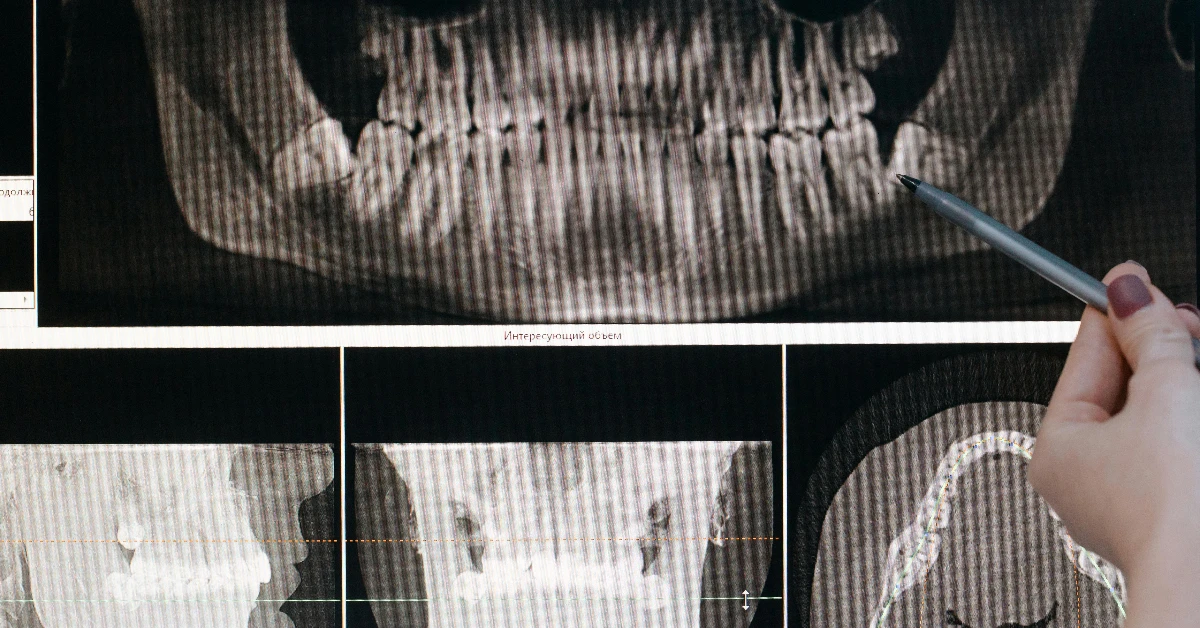

C’est le point de départ. Votre orthodontiste effectuera un bilan complet :

• Examen clinique de votre bouche et de votre visage.

• Prise de photographies et de radiographies (panoramique, téléradiographie de profil).

• Prise d’empreintes de vos dents (avec une pâte ou un scanner numérique 3D).

Ce “dossier orthodontique” est essentiel pour poser un diagnostic précis et élaborer un plan de traitement sur mesure.